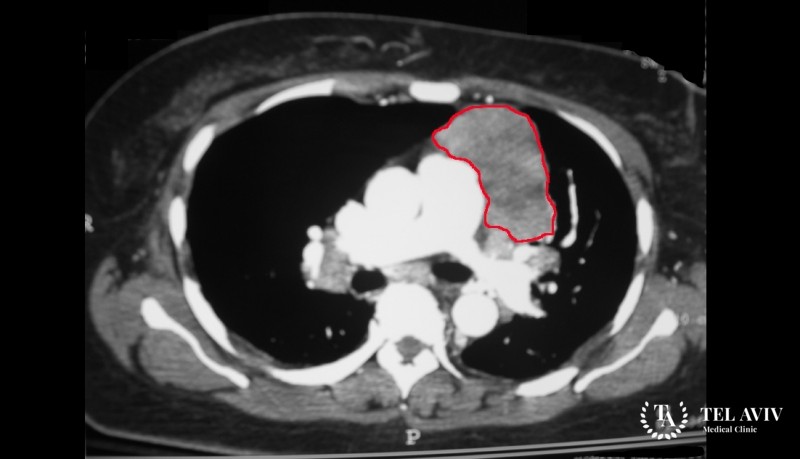

Перикардиальная киста представляет собой доброкачественное образование овальной формы, состоящее из бесцветной жидкости и имеющее соединительнотканные стенки с сосудами и жировыми клетками. Большинство кист средостения относятся к виду патологий с врожденным происхождением. Приобретенные кисты образуются обычно на фоне воспалительного процесса или после травмы грудной клетки, из-за полученной гематомы. Кисты могут содержать одну или несколько камер, сращиваться с перикардом широким основанием или ножкой. Перикардиальные кисты могут иметь различное клиническое течение, вызывать серьезные осложнения, такие как эмболия. Кисты могут воспаляться, наполняясь при этом гноем, вызывать нарушения в работе сердца.

- КТ.